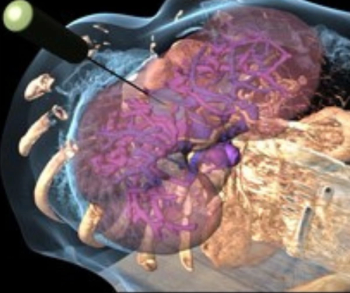

Featuring the previously FDA-cleared BioTraceIO Vision and BioTraceIO Precision modalities, the BioTrace software suite combines real-time ultrasound guidance and advanced AI technology to help bolster outcomes with liver tumor ablation therapy.